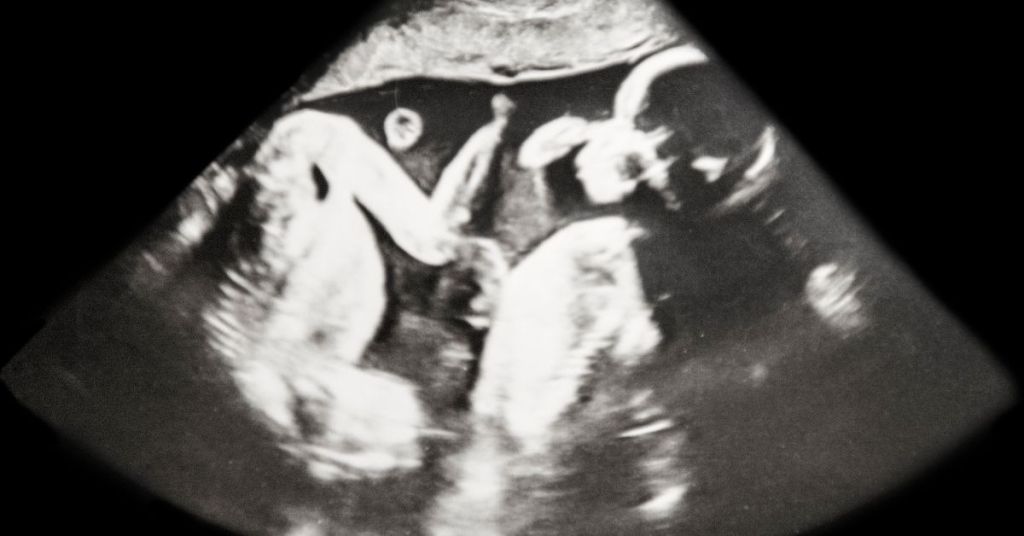

El diagnóstico de la superfetación se realiza con un ultrasonido de rutina. Normalmente cuando el ginecólogo hace la ecografía se da cuenta de que existen dos placentas y dos embriones con un grado de desarrollo distinto. Se suele apreciar una discrepancia de tamaño, lo cual no solo se debe a la diferente edad gestacional sino también a que uno de los embriones puede bloquear o alterar el crecimiento del otro.